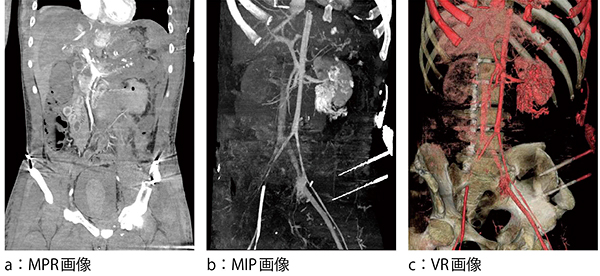

症例2は,高エネルギー外傷による活動性出血である。救急受け入れで骨盤骨折を指摘され,創外固定された後にtrauma panscanを施行した。VR画像により創外固定具の確認ができた(図5)。骨自動除去のアイテムを使用しても完全に除去できなかったが,オパシティの調節やマルチレイヤーを駆使して骨以外の血管や臓器をMIP画像(図6 b)として描出した。VR画像(図6 c)により活動性出血の血管を同定し5),6),IVRによる塞栓術および臓器破裂による緊急外科手術に至った。

図6 症例2:活動性出血画像の描出

骨を自動除去できない場合は手動での画像作成になるが,時間的な制約を考慮して骨と血管を分離する技術が必要となる。特にMIP画像は,骨を除去して造影された周辺臓器や組織を描出しなければならない。 (1)まず診断に必要のないゴミを消去する。(2)マルチレイヤーを使用する。(3)全体のVR画像のオパシティを調整して骨のみを薄く描出する。(4)全体のVR画像から(3)を引き算して大まかな血管を描出する。(5)全体のVR画像から(4)を引き算して骨のみを描出する。この時血管が残っていないかを確認する。(6)全体のVR画像から(5)を引き算することで骨以外の軟部組織が描出される。(7)それぞれをマルチレイヤーに保存して,MIP画像やVR画像を作成する。